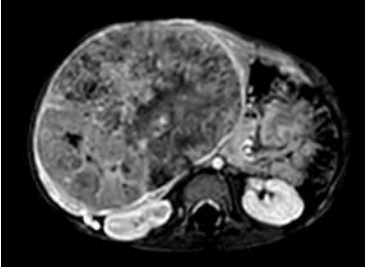

Menino, 2 anos e 6 meses, com aumento de tamanho do abdominal há meses, maior em hipocôndrio e flanco direitos. Ao exame físico: circulação colateral evidente e hepatomegalia endurecida a 8cm do rebordo costal direito.

Em relação ao diagnóstico de sua principal hipótese, é correto afirmar: